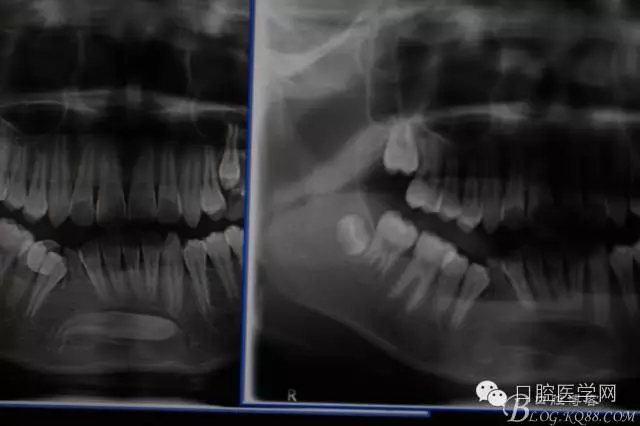

橫位埋伏3的取出術(shù)